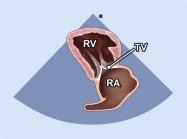

| 2.6. Mặt cắt trục dài cạnh ức qua buồng nhận thất phải |

||||||||

|

|

Cửa sổ siêu âm cạnh ức

Mặt cắt trục dài cạnh ức Ngả đầu dò xuống dưới hướng về phía đùi phải của bệnh nhân |

Nhĩ phải (RA) Van ba lá (TV) Thất phải (RV) |

|||||